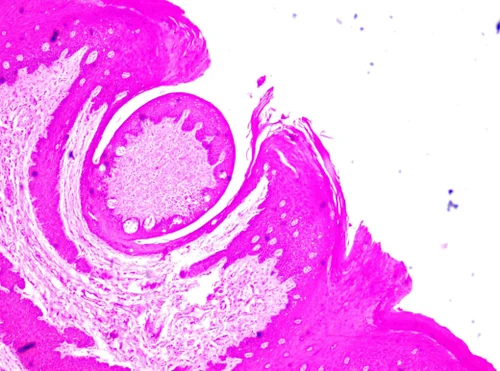

المادة هذه تعتمد بشكل كبير على الفهم البصري، وما ينفع تحفظها بدون ما تشوف الأنسجة بعينك. عشان كذا صممت هذا الكورس عشان نمشي مع بعض خطوة بخطوة من أول نظرة تحت المجهر لحد ما تبقى قادر تشخص أي نسيج بمجرد ما تشوف الشريحة.

اعتماد على الصور: راح نشاهد سوا شرائح مجهرية حقيقية ورسومات توضيحية عشان تثبت المعلومة بشكل ما تنتسى.